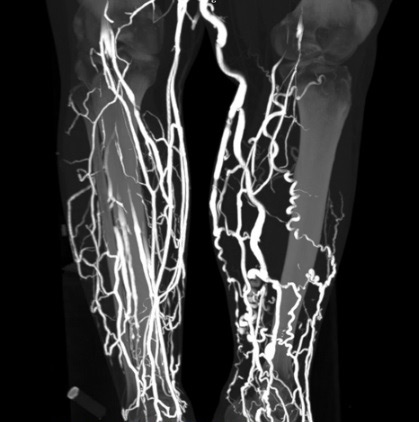

пример результатов КТ-флебографии ног, сделанной для более эффективной подготовки к операции флебэктомии

В протоколе флебографии нижних конечностей при нормальной рентгенологической картине можно увидеть такие фразы, как функция клапанного аппарата вен сохранена, проходимость вен в норме, дефектов наполнения или «обрыва» контраста не обнаружено. В случае наличия тромбоза указанные изменения присутствуют, обусловленные полной или частичной непроходимостью венозного просвета для контраста.